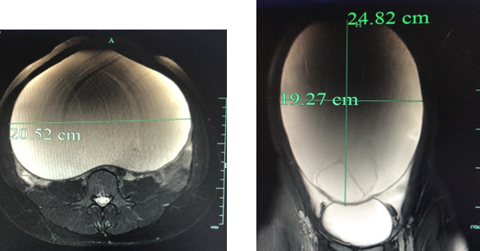

富阳16岁女高中生突然发胖,一个月后肚子藏不住了!

每逢佳节胖三斤,仔细一看三公斤。今年春节后,16岁女孩小欣(化名)就开始莫名其妙地“发胖”,一个多月下来,她的肚子像吹了气的气球一般,一天比一天大,犹如六七个月的孕妇。 “肚子涨到感觉随时要爆炸”,忍无可忍的小欣,最终来到杭州市第一人民医院检查。没想到,这一检查,连医生都惊掉下巴…… (一)我的肚子涨得要爆炸了”才过一个月,少女肚子大得像孕妇 家在富阳的小欣,今年16岁,正在读高一。今年春节,小欣